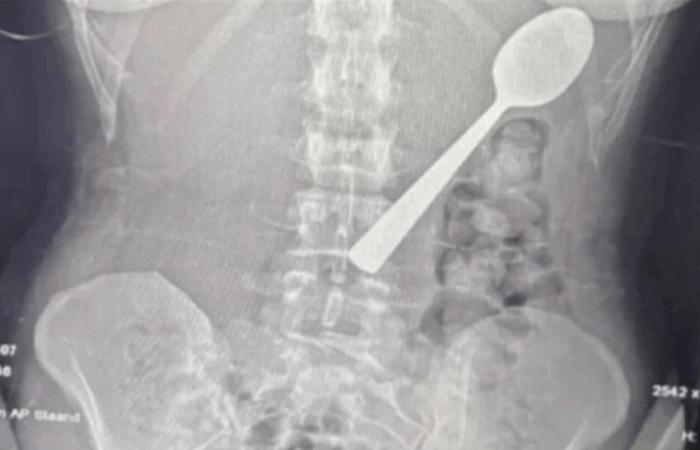

وعند مراجعة الأطباء، تبيّن أن الملعقة أكبر من أن تمر عبر الجهاز الهضمي بشكل طبيعي، ما استدعى تدخلاً عاجلاً. وبعد انتظار يومين تحت المراقبة، خضعت ريمي لعملية منظار معدة تحت التخدير الموضعي، حيث قام الأطباء بتدوير الملعقة بحذر داخل المعدة لسحبها، ما تسبب بنزيف طفيف والتهاب مؤقت في الحلق.

وأكد الفريق الطبي عدم تسجيل مضاعفات دائمة، فيما قررت ريمي الاحتفاظ بالملعقة بعد استخراجها كـ"ذكرى" للحادثة، مشيرة إلى أن شريكها يخطط لتحويلها إلى قطعة فنية داخل المنزل.